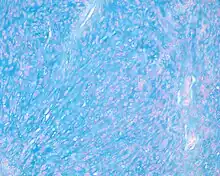

Alcian blue (pH at 2.5) stains the myxoid background material brightly blue in this ectomesenchymal chondromyxoid tumor of the tongue.